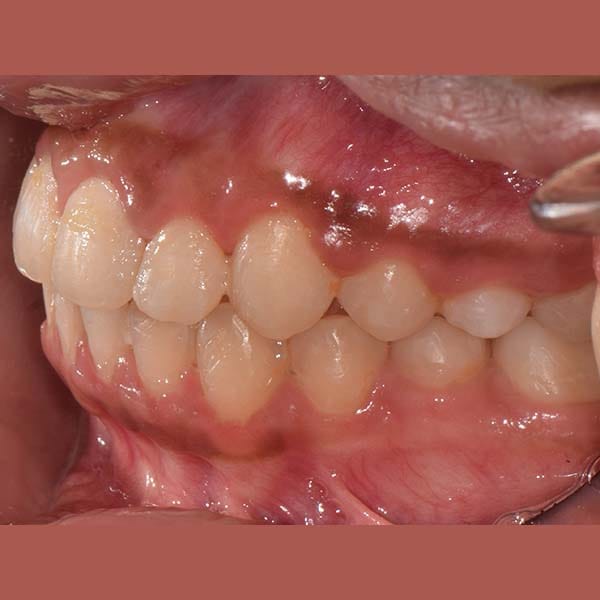

بعد

ابتسامة جميلة جدا